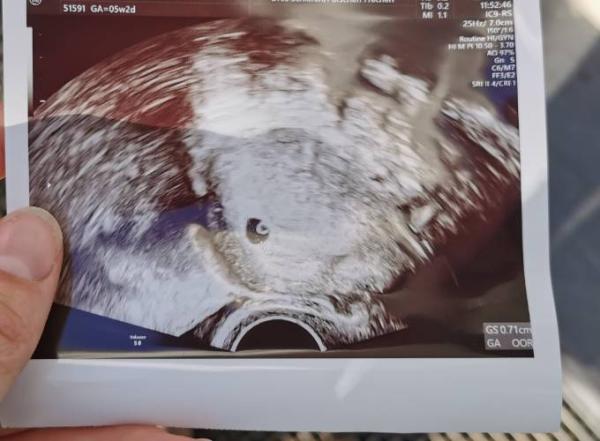

1.US und es sieht sehr sehr gut aus im Vergleich zum letzten Mal 5+2 derzeit Gs 0.71 Mal sehen ob sie noch korrigiert. Der Wert ist schon sehr gut (lt. Tabelle bei 5+3) Meine Ovus haben ja auch was anderes gesagt als die Tempimethode...

Bild zu 1. Termin US - Forum für Juli - Mamis